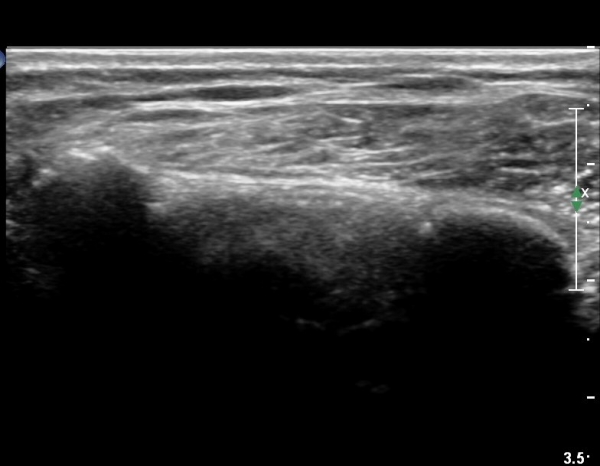

±Ø»ó°Ç Á¶´ã¸é°Ë»ç¿¡¼­ ±Ø»ó°ÇÀÇ ÅðÇ༺º¯È­È­ ºÎºÐÀûÀÎ ÆÄ¿­ÀÌ  °üÂûµÇ¸é ´ë°áÀýÀº

ºñÈĵǾî ÀÖ´Ù(»çÁø 6, 7, 8).